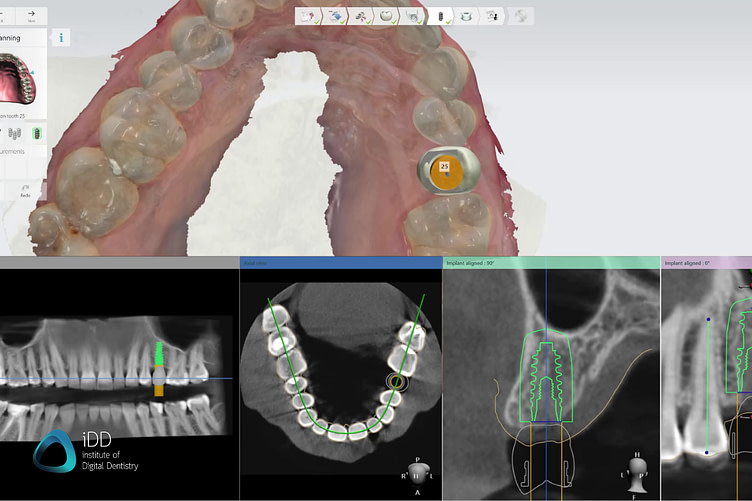

Specialized software is used to plan the implant surgery ad design the surgical guide based on the digital models obtained.

In this case, we used Implant Studio by 3Shape, but there are many implant planning software available, some of them even for free with a pay-per-export option. 3Shape is just our favorite by far due to its ease of use and slick workflow.

Most software follows a so-called restoratively-driven implant planning workflow. This means, that a digital model of the future crown/restoration is used to help you plan out the ideal implant position. This way, you can prevent placing an implant with a screw channel opening coming through the buccal aspect or cusps.

Using the implant planning software, several factors such as adjacent teeth and bone density can also be addressed and accounted for. Additionally, you will be prompted to mark the inferior alveolar nerve when planning for a mandibular implant, and it makes it easy to account for sinuses as well as maxillary implants.

Within the same software, you get to choose your preferred implant brand, as well as the fixture type, width, and length for the implant company of your choice. This is done by importing the digital library of the brand of implant you want - something that can be obtained from the sales rep/company website. Implant planning software is generally open, meaning that you can download the digital libraries for any implant company.

For a restorative-driven workflow, a digital tooth mock-up is used to help find the most aesthetic and functional implant position. CBCT data help you account for bone density, sinus, or inferior alveolar nerve.